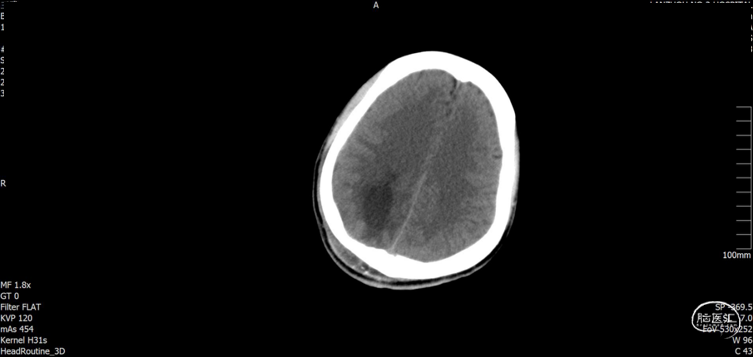

术后随访

术后CT